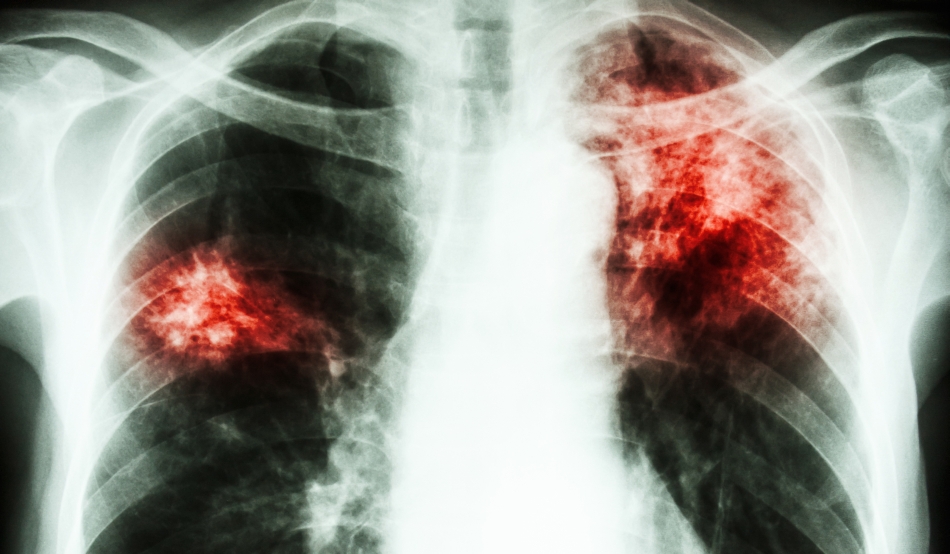

Simptomele clasice ale tuberculozei active sunt tusea cronică, cu striuri de sânge, spută, febră, oboseală cronică, transpirația nocturnă și scăderea în greutate (TBC se numea în trecut „boala consumării”, din cauza scăderii în greutate a persoanelor infectate). Infectarea altor organe provoacă o varietate mare de simptome. Diagnosticul tuberculozei active se face prin radiologie, (cunoscută drept radiografie toracică) prin examinare microscopică și cultură microbiologică a fluidelor corporale. Diagnosticarea tuberculozei latente se face prin testul cutanat la tuberculină (TCT) și analize de sânge. Tratamentul este anevoios și presupune administrarea mai multor antibiotice pentru o perioadă îndelungată de timp (minim 6 luni). De asemenea, contactele sociale ale persoanei infectate se examinează și tratează, dacă este necesar. Rezistența la antibiotice constituie o problemă în creștere în cazul tuberculozei rezistente la medicamente multiple (MDR-TB). Pentru a preveni TBC, oamenii trebuie examinați anual (radiografie pulmonară) pentru depistarea bolii și educați să aibă o viață echilibrată ca să nu le scadă imunitatea și să fie vulnerabili la infecție, copii mici trebuie vaccinați cu bacilul Calmette–Guérin pentru prevenirea îmbolnăvirilor cu forme grave care pot lăsa sechele majore (tuberculoza miliară, meningo-encefalita TBC).